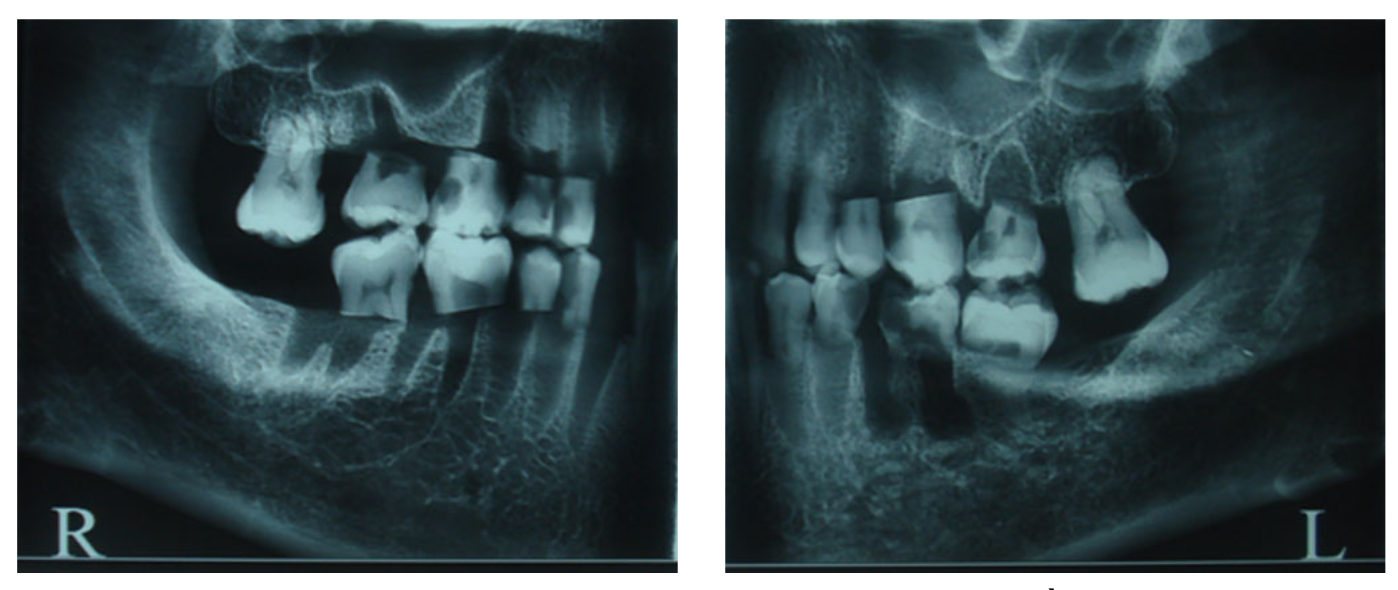

2.1 Dataset Preparation

- Sample: 발치된 인간의 소구치 및 대구치 80개를 사용하여 총 160개의 인접한 표면을 평가 대상으로 설정했다.

- Imaging Modalities:

- Ground Truth (Gold Standard): 촬영 후 치아를 물리적으로 절단하여 입체 현미경으로 충치 유무 및 진행 정도를 4단계 척도로 정밀 판독했다.